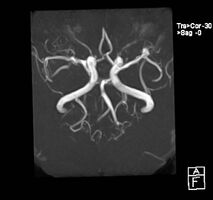

| Aneurysm of the basilar artery and the vertebral arteries. | |

CT angiography showing aneurysm measuring 2.6 mm in diameter at the anterior communicating artery

Aneurysms in the posterior circulation (basilar, vertebral and posterior communicating artery) have a higher risk of rupture. Basilar artery aneurysms represent only 3–5% of all intracranial aneurysms but are the most common aneurysms in the posterior circulation.